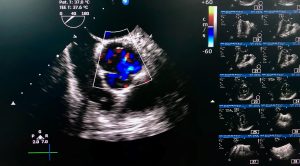

Sutter Health Earns Top Heart Imaging Accreditation

Transesophageal echocardiogram (TEE) shown normal Aortic valve (AV) opening in parasternal short axis view under color doppler